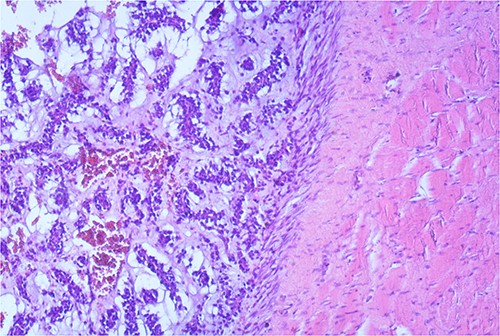

The macroscopic pathology report revealed the total dimension of the removed tissue to be 10.5 × 8.5 × 10.5 cm. However, the tumor itself had dimensions of 8 × 7.5 × 7 cm, surrounded by a pseudo capsule. The tumor was described to be multicystic, formed by loculi filled with hemorrhagic and partially with yellowish gelatinous myxoid content. In its periphery, yellowish tumor tissue was present (Fig. 3). Microscopic findings described a tumor made of myxoid stromal nodules and small capillaries concentrically surrounded by monomorphic round cells with mild nuclear pleomorphism. Large pseudo-angiomatous spaces filled with blood were seen in some of the nodules. Part of the nodules was hypocellular, made mostly by myxoid stroma and stellate cells. A thick fibrous pseudo capsule with numerous multifocal deposits of hemosiderin deposits was present peripherally. Tumor tissue infiltrates the abdominal wall muscles (Figs 4 and 5).

Small capillaries lined by relatively monomorphous round cells, with mild pleomorphism and sparse mitotic activity, surrounded by myxoid stroma (HeEo, ×100).